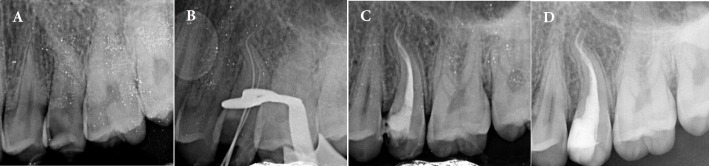

单锥体技术,也称为液压凝结技术,在牙髓病学中被广泛采用。然而,上述方法存在一定的局限性,特别是在冠状密封以及圆形横截面的水凝胶(GP)的冠状三分之一与半圆形或椭圆形横截面根管的冠状牙本质壁的适应性方面。本文通过两个病例报告介绍了冠状垂直冷凝(CVC)技术,旨在增强类似情况下 GP 与根管壁的适应性。事实上,冠状垂直冷凝技术融合了暖垂直冷凝技术和单冠技术的不同方面。在 CVC 中,放置主 GP 锥体后,立即在距根管口几毫米处插入电热载体,以去除主 GP 锥体的冠状部分。随后,使用手动堵塞器在垂直方向凝结 GP,并使用融化的 GP 回填冠状空间。CVC 技术的实施表明,GP 与管壁的冠状适应性得到了改善。上述技术似乎很有益处,尤其是在封闭严重弯曲的根管或最终预备形状为可变锥度的根管时。

The single-cone technique, also known as the hydraulic condensation technique, is widely employed in endodontics. However, the aforementioned method is presented with certain limitations; specifically concerning the coronal seal and the adaptation of the coronal third of a master gutta-percha (GP) with a round cross-section to the coronal dentinal walls of root canals with semi-round or oval cross-sections. Through two case reports, the current article introduces the coronal vertical condensation (CVC) technique; aiming to enhance GP adaptation to canal walls in similar scenarios. In fact, the coronal vertical condensation technique amalgamates the different aspects of warm vertical condensation and single-cone techniques. In CVC, following the placement of the master GP cone, an electrical heat carrier is inserted immediately a few millimeters apical from the canal orifice to remove the coronal portion of the master GP cone. Subsequently, a hand plugger is used to condense GP in the vertical dimension, and the coronal space is backfilled using melted GP. The implementation of CVC technique has demonstrated an improved coronal adaptation of GP with canal walls. The stated technique seems beneficial; especially in the obturation of severely curved canals or root canals with a final preparation shape of variable taper.